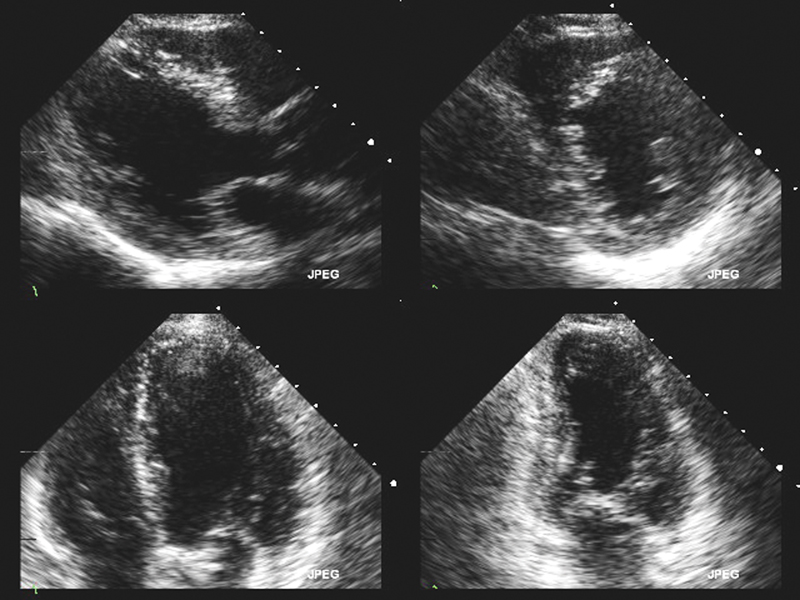

فحوصات تشخيصية لبعض امراض القلب والشرايين التاجية